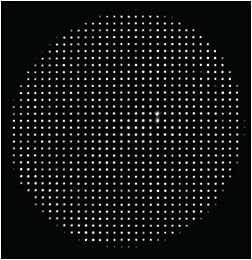

HIGH-RESOLUTION SENSOR MAXIMIZES CAPTURE RATES

- High-resolution Hartmann-Shack wavefront sensor (5 x higher than previous generation)

- Fourier reconstruction algorithms using up to 1257 micro-refractions over a 7-mm wavefront

- Improved accuracy and ability to measure complex wavefronts and highly aberrated eyes